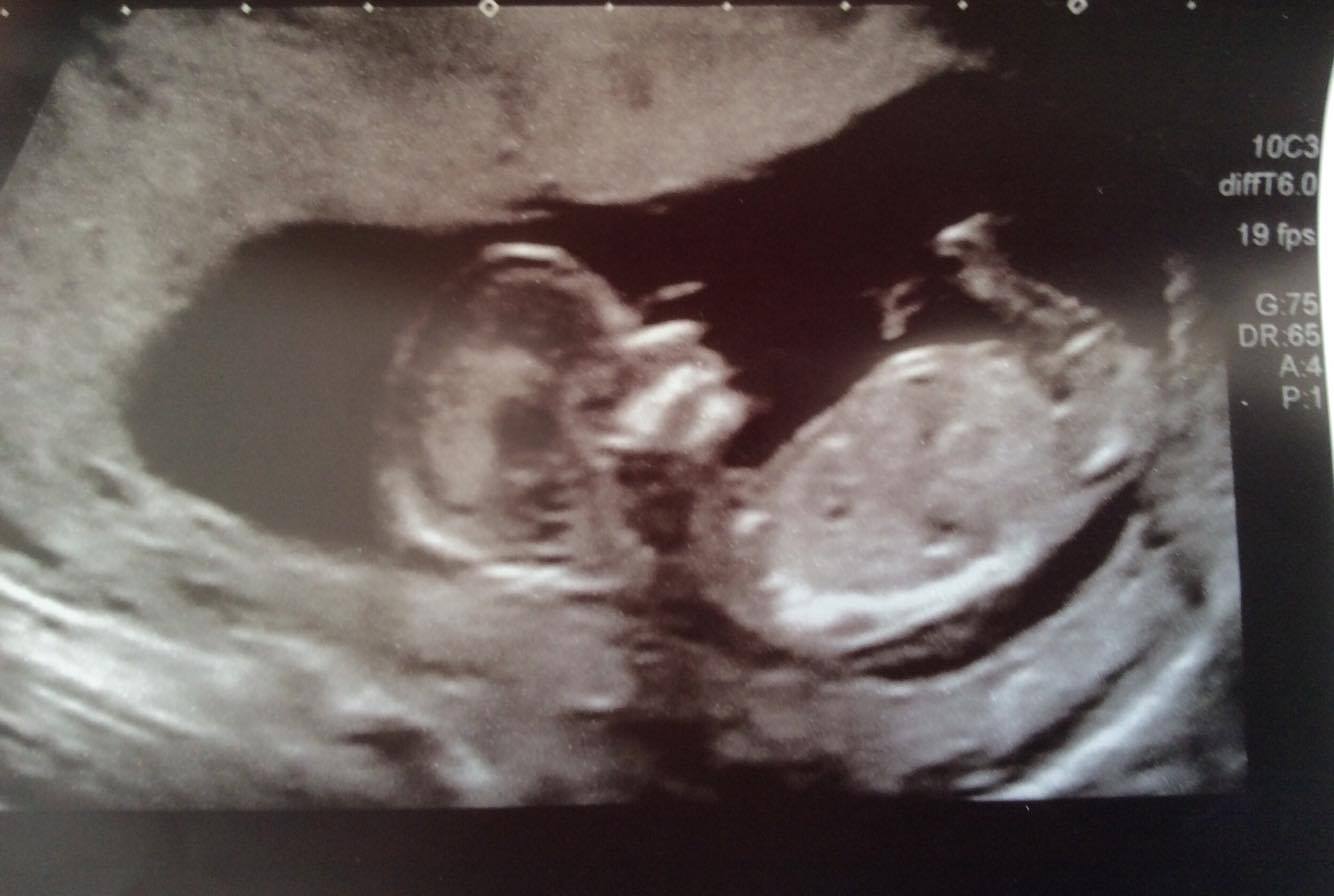

Ramzi & Nub Guesses Please? x Semi Sway Inc

Attachment 30598

Attachment 30599

Attachment 30600

I was wondering if some of you guys would be able to give me some gender predictions based on my early scan at 8w 1day and my nub scan at 13w 1day. I am useless at this and trying hard to figure them out but need some help please.